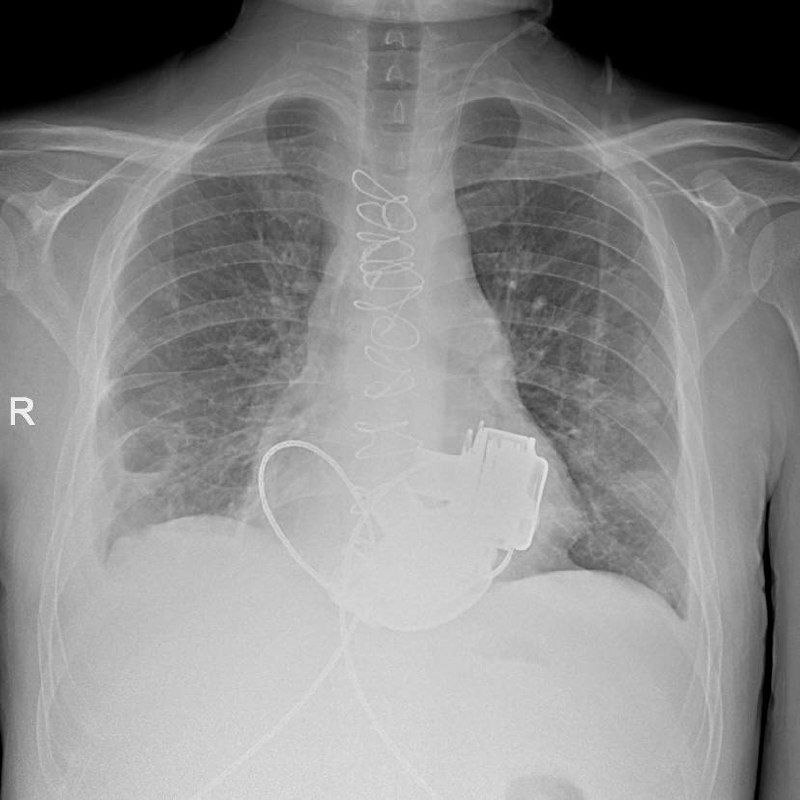

Как рассказали в пресс-службе комитета по здравоохранению Петербурга, в стационар Мариинской больницы 36-летний Антон поступил сразу с несколькими тяжелейшими диагнозами. Его показатели работы сердца были такими, будто человек уже не жив, а мёртв. Трансплантация сердца, которая показана в таких ситуациях, была невозможна из-за ряда осложнений. Тогда медики приняли решение провести непростое кардиохирургическое вмешательство - имплантацию искусственных желудочков. Обычно пациентам вживляют одно такое устройство, однако Антону потребовалось сразу два прибора. Потом пульс на запястье или шее у таких людей не прощупывается.

"Операция продолжалась около 4 часов. Для наших специалистов самым сложным было синхронизировать работу двух искусственных желудочков сердца, но с этой задачей мы успешно справились", - рассказал главный внештатный специалист по сердечно-сосудистой хирургии комитета по здравоохранению Санкт-Петербурга, академик РАН Геннадий Хубулава.

Послеоперационный период для мужчины был не простым, однако сейчас он уже научился жить с двумя приборами в теле и готов к выписке.

В региональном комздраве назвали имплантацию искусственных желудочков "мостиком" к трансплантации сердца. Пациент надеется, что вскоре сможет получить донорское сердце.